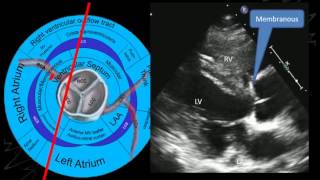

A/Prof Greg Scalia: Imaging the aortic valve

A/Prof Greg Scalia provides a comprehensive overview of aortic valve anatomy and advanced imaging t…